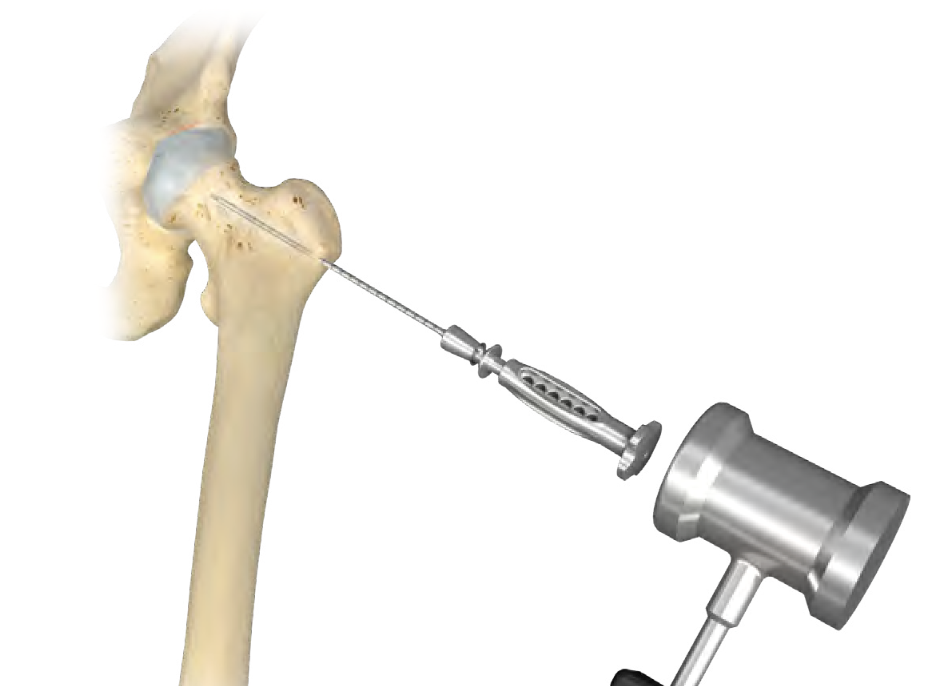

Central Core Decompression Techniques

Zimmer PerFuse Percutaneous Decompression System

Technique

- AP and lateral xray

- entry point through greater trochanter

- above lesser trochanter to reduce fracture risk

- enter site of AVN

- overdrill

- +/- bone graft / vascularized bone graft / tantalum rod / BMAC (bone marrow aspirate concentrate)